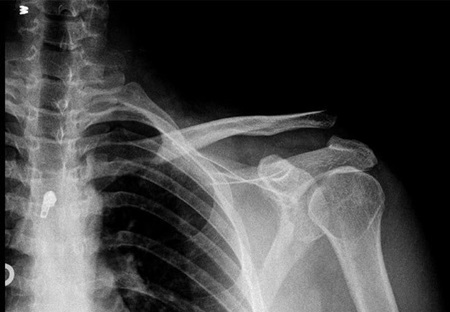

Raquitismo se caracteriza por aqueles que são afetados desenvolvem uma série de deformidades esqueléticas que são vistos a olho nu, embora seja verdade que existem diferentes níveis e tipos de raquitismo, mas todos têm em comum deformidades produzidas no osso. Basicamente, esta doença é caracterizada pela desmineralização óssea progressiva. Isto é porque, tal como indicado anteriormente, a dificuldade de que o organismo tem de absorver o cálcio e fósforo, essenciais para a manter um adequada saúde óssea.